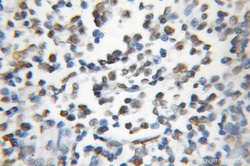

11726-2-AP IHC

Immunohistochemistry

Method: